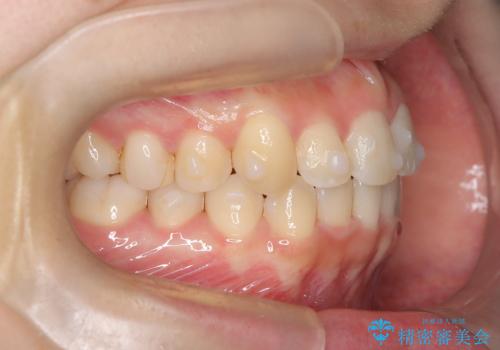

- 右上の前歯(2番)が下の歯より内側に入っている反対咬合を主訴にご来院されました。精密な検査の結果、この反対咬合を解消するためには、右上の歯列に前歯を出すためのスペースを確保する必要があると判明しました。患者様のご希望に合わせ、透明で目立たないインビザライン(マウスピース矯正)による治療計画を立案。奥歯全体を奥へ動かす遠心移動でスペースを作り、反対咬合を解消することを目指します。

今回の矯正治療では、透明なマウスピース型の装置インビザラインを使用しました。治療は、緻密なデジタル計画に基づき、奥歯から順に歯列全体を後方へ移動させる遠心移動を実施し、前歯を前に出すためのスペースを確保しました。このスペースを利用して、内側に入り込んでいた右上2番をスムーズに前方に誘導し、正常な咬み合わせへと改善。目立たないインビザラインで、機能的な咬み合わせと美しい前歯の並びを獲得していただけました。